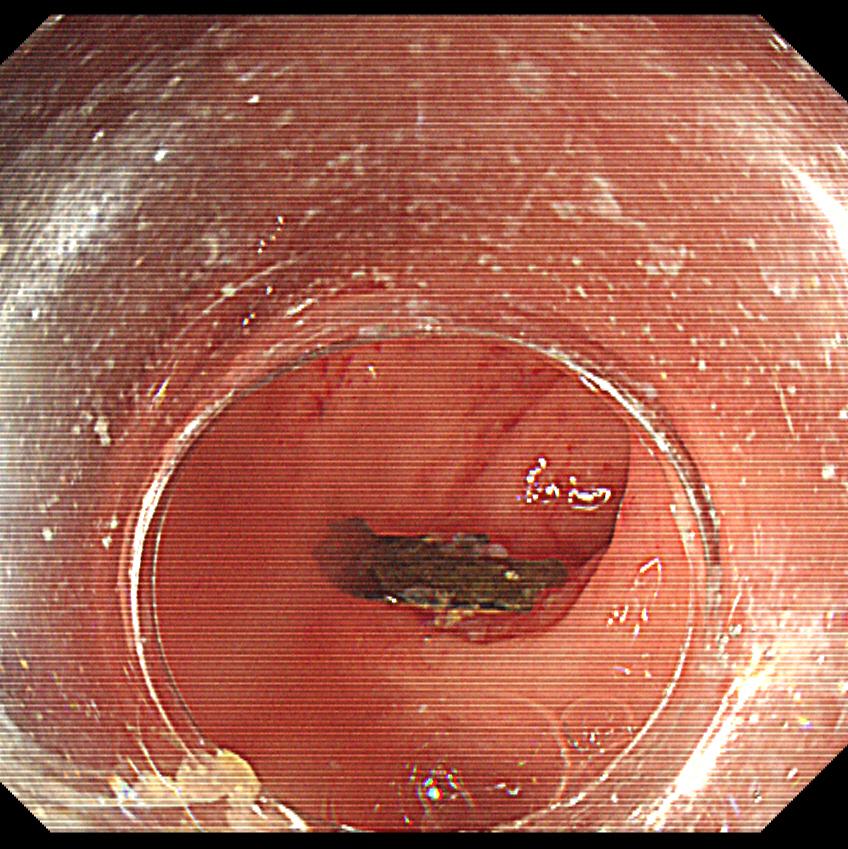

1、肠镜系统察看阑尾窝红肿糜烂

图片